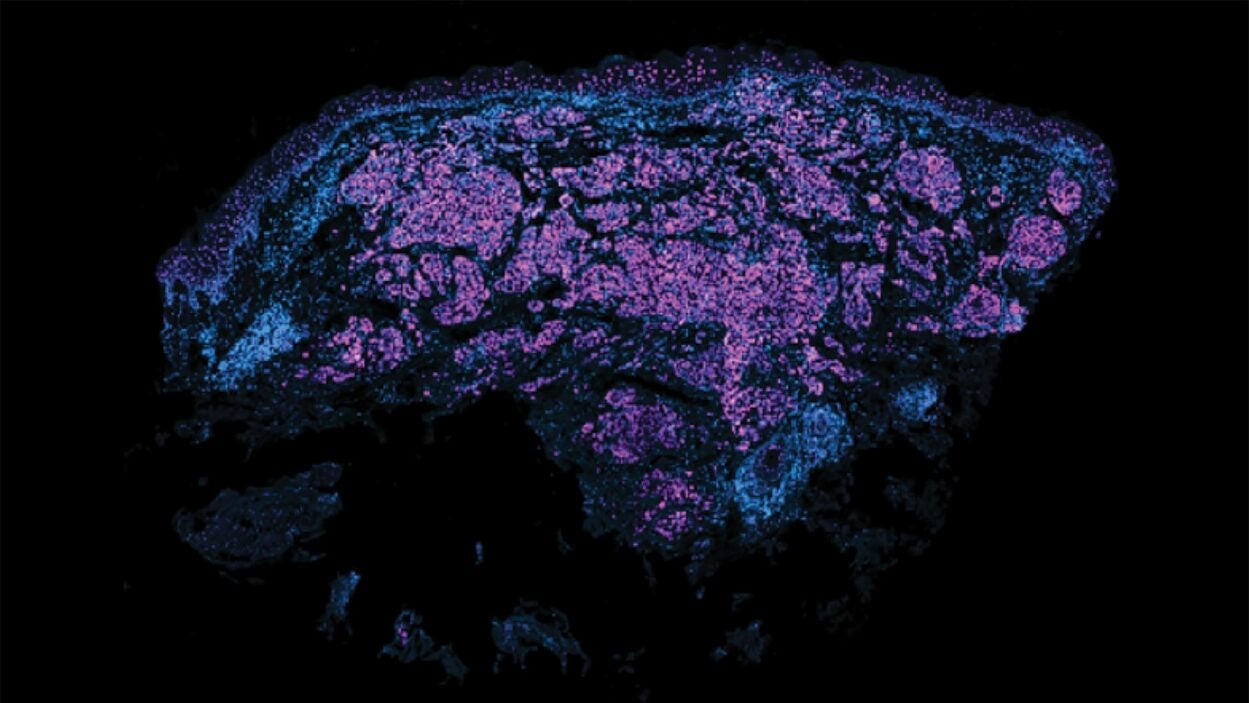

An angry peacock is no joke. Like the colorful bird and its tall tail feathers, cancer biology can make for some eye-catching images. Read the story »

A tumor is not just a tumor. It’s a complex ecosystem scientists unpacked at the CSHL meeting, Biology of Cancer: Microenvironment & Metastasis. Read the story »